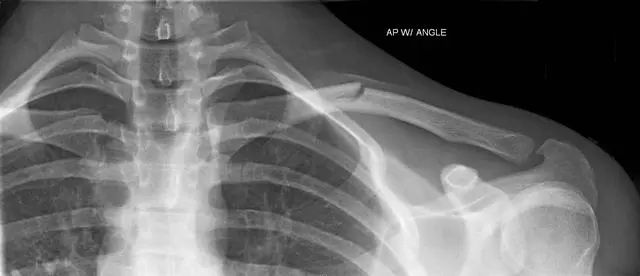

新生小孩锁骨骨折怎么办?新生儿锁骨骨折是新生儿娩出过程中最常的骨折。新生儿锁骨骨折治疗简易,预后良好,没有并发症,故不应采取任何过激的治疗方法新生婴儿的锁骨骨折,大多数是产伤,而且几乎都是顺产的,这种骨折比较常见。

有些出生后,家人并不知道锁骨发生骨折,只是骨折的这一边手臂活动比较少,引起雷注意,一拍片,才发现有骨折。有的是给孩子洗澡穿衣服的时候,孩子哭泣,另一边则没有这样的情况,引起家人都注意,才发现的。

也有的家长比较细心,看见锁骨的地方两边不一样,一边明显鼓起来,摸或者按压会引起孩子哭闹挣扎,引起注意,去拍片才发现有骨折。

新生儿锁骨骨折恢复较快,一般都于骨折的一个礼拜出现骨膜增生及骨痂形成,两年内随着小儿的生长发育,肩部增宽,锁骨的畸形均可自行消失,完全恢复原状,不会留有后遗症。

一般在10天左右,就会愈合,不需要任何治疗。虽然对位对线不好,愈合后有个鼓起来的包包,硬硬的,以后会慢慢塑形,包包会逐渐消失。所以是不需要担心的。